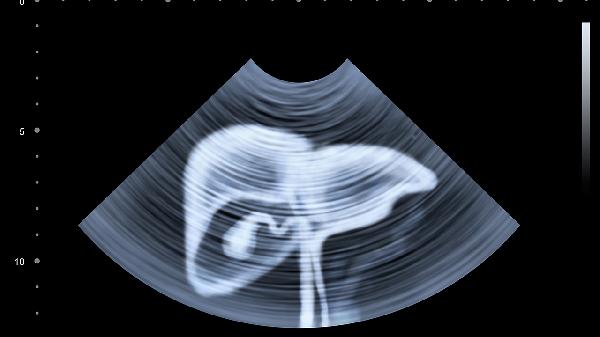

規(guī)范抗病毒治療是延長壽命的核心措施。目前直接抗病毒藥物如索磷布韋維帕他韋片、格卡瑞韋哌侖他韋片等可達到較高治愈率?;颊咝鑷栏褡襻t(yī)囑完成全程治療,避免自行停藥。治療期間每4-12周需檢測HCVRNA水平評估療效,治愈后仍需每年復查病毒載量。肝功能異常者需每3-6個月檢查ALT、AST等指標,肝硬化患者應增加腹部超聲和甲胎蛋白檢測頻率。合并脂肪肝患者需控制體重指數在24以下,通過低脂飲食和每周150分鐘有氧運動改善代謝。戒除酒精可降低肝細胞損傷風險,每日酒精攝入量應控制在男性25克、女性15克以下。門靜脈高壓患者需限制鈉鹽攝入,每日食鹽不超過5克有助于減少腹水形成。